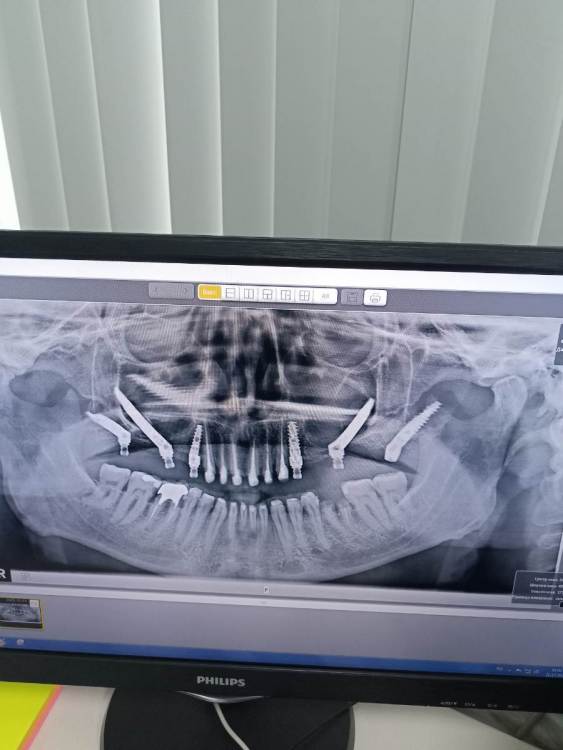

VelikoMu4ennik Опубликовано 27 января, 2023 Автор Поделиться Опубликовано 27 января, 2023 Я так понял скуловая имплантация пока темный лес для подавляющего большинства и людей и стоматологов. Вообщем напишу, как прошедший данную экзекуцию, что не стоит она того. Чудовищно-травматичная процедура с рисками ужасных последствий вплоть до проблем со зрением. Вернись я сейчас назад, в жись бы на зигомы не согласился, ограничился бы классическими в зоне 4 и птирадаптелями в зоне 8, вполне себе надёжная фиксация на них аккуратного сьемника с минимальным каким нить базисом была бы да и норм Ссылка на комментарий

VelikoMu4ennik Опубликовано 27 января, 2023 Автор Поделиться Опубликовано 27 января, 2023 (изменено) А вот такую штуку в черепе заполучить....от одного ее вида страшно) Изменено 27 января, 2023 пользователем VelikoMu4ennik Ссылка на комментарий

Irouil Опубликовано 27 января, 2023 Поделиться Опубликовано 27 января, 2023 Скуловые импланты в некоторых ситуациях - единственный выход для пациентов, расчитывающих на протезирование. Другой вопрос - показания к ним. 1 1 Ссылка на комментарий